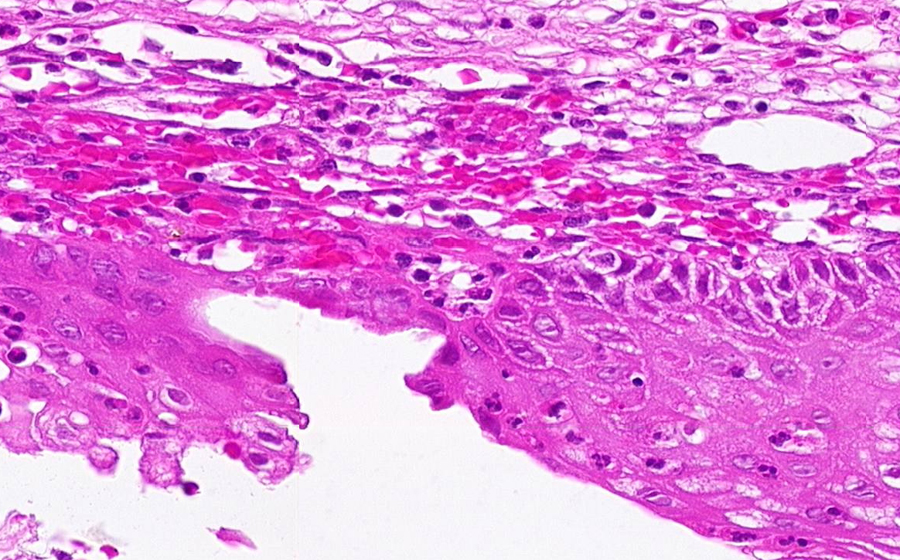

Slide 3: Chronic cervicitis and metaplasia

Histologic section of cervix from a patient with chronic cervicitis (click here to review normal tissue)

Image 5 - 400X

Slide 3 - Image 5